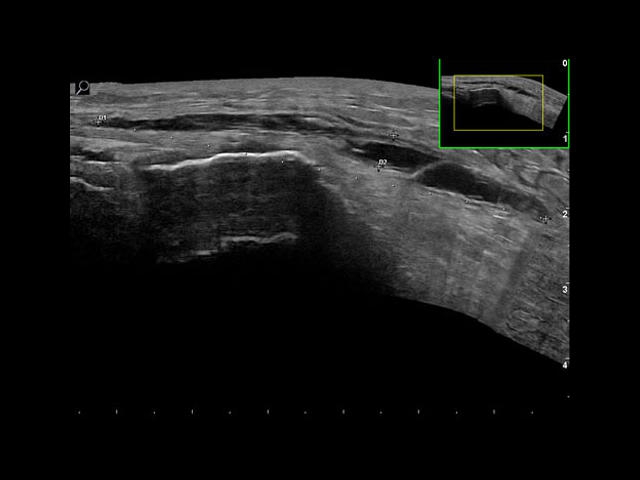

Esaote MyLab Alpha

Esaote MyLab Alpha - это мощная диагностическая система экспертного класса с очень компактными размерами. По качеству картинки Alpha не уступает стационарным аппаратам благодаря широким возможностям визуалиции и последним разработкам итальянской компании Esaote.

Esaote MyLab Alpha представляет собой передовую диагностическую систему с инновационными технологиями для углубленных исследований в различных областях медицины.

• Технология ElaXto для оценки эластичности тканей в реальном времени

• Высокочувствительные датчики iQ Probe для точной диагностики